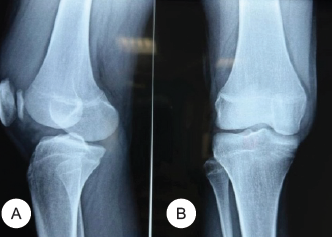

Management of Large Osteochondral Fracture of the Patella in an Adolescent: A Rare Case Report

Siddhart Yadav ,Chiranjeevi K P , Akash Singh Jadon , Sameer Pandey

………………………………p.216-221